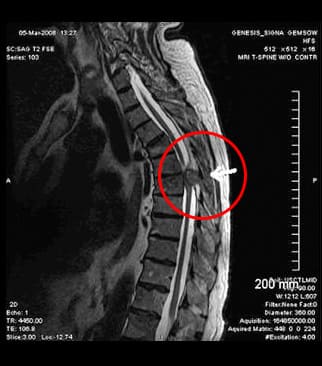

Das EKG zeigte, dass es meinem Herzen gut ging. Ich ließ viele Untersuchungen über mich ergehen, bis man herausfand, dass ich eine thorakale Osteochondrose hatte. Damit hatte ich nicht gerechnet! Ich treibe Sport, gehe zum Yoga, schlafe auf einer orthopädischen Matratze. Alles umsonst...